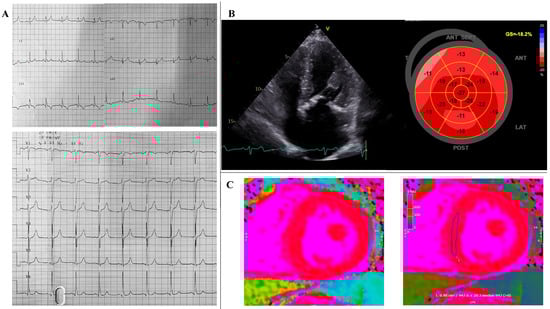

2. Case Report